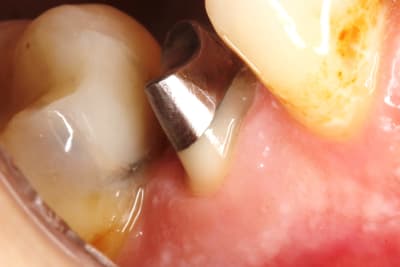

ce matin , je viens de finaliser 1 ccc .

taille profonde sur une fracture vestibulaire . il a fallu prendre l empreinte au fil , avec des limites vest profondes . là si j avais fait un prov , j aurais eu une rétraction le jour du scellement , et à coup sur perdu de la gencive attachée , donc pas de prov .

pourtant ç est une coquette :-)) , ben non , faut ce qu'il faut . elle n a eu le choix que de sa couleur : " bien bien blanc , voyez docteur "

photo de l empreinte la semaine passée , et avant scellement aujourd’hui , et couronne ccc scellée .